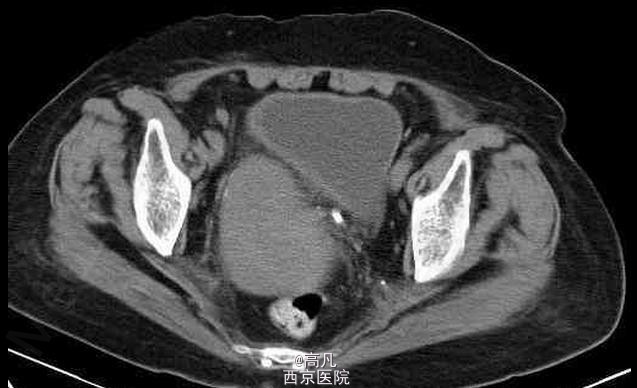

临床一例子宫内膜癌

子宫内膜癌

女,70岁,因近日来阴道不规则出血前来就诊

不规则阴道出血,常为少量至中等量的出血,有稀薄的白色分泌物 辅查CT,MRI,CT表现常可见宫体不均匀增大, MRI示子宫内膜增厚,T2WI上内膜信号不均,部分可见宫内低信号连接带中断

子宫内膜癌 处理:以手术为主,配合化疗及放疗